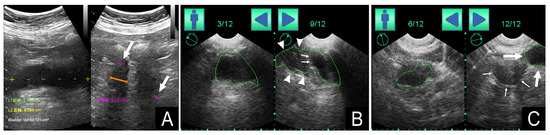

3.5. Correlation between Bladder Shape and PVRU Volume